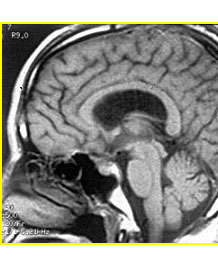

沈建康主任论文:颅内巨大动脉瘤的显微外科手术治疗

作者: 沈建康 赵卫国 卞留贯 成侃 孙青芳 胡锦青 发表于: 中华神经外科杂志 [摘要] 目的: 研究影像诊断技术和改进显微外科手术技术,以提高颅内巨大动脉瘤的手术疗效。 方法: 回顾性分析作者自1985年1...【详细】

沈建康主任论文:鞍结节脑膜瘤的手术入路和技巧

作者: 沈建康 赵卫国 卞留贯 濮春华 蔡瑜 发表于: 中华神经外科杂志 摘要 目的: 探讨鞍结节脑膜瘤的手术入路和手术技巧,以改善手术治疗的效果。 方法:回顾性分析我科1985年1月至2004年12月手术治疗的...【详细】